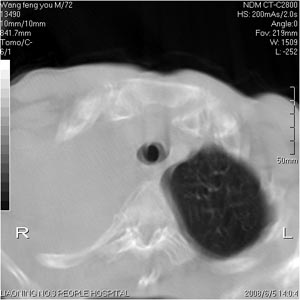

患者:男 72岁 右肩痛半年,近日来咳血,就诊.

右肺中心型肺癌并上叶不张,右侧胸腔积液,做镜检吧.

典型右中心型肺癌并右肺上叶不张,左肺转移,右胸腔积液。

考虑:右肺上叶中心型肺癌伴肺不张、肋骨转移、肩胛骨转移、右侧胸腔积液。

1.考虑:右肺上叶中央型肺癌并右肺上叶不张及右侧多发肋骨、上纵隔淋巴结及左肺转移。

2.右侧胸腔积液。